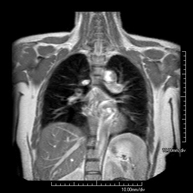

- Tòrax

- RM del Mediastí

Prova diagnòstica no invasiva que consisteix en l'obtenció d'imatges d'alta definició anatòmica del mediastí mitjançant l'ús d'un camp electromagnètic i ones de ràdio (amb un emissor i un receptor). No utilitza radiació ionitzant. El mediastí és la part central de la caixa toràcica que inclou el tim, els grans vasos (aorta toràcica, vena cava inferior i superior, etc.), el cor, la tràquea i els bronquis principals, els ganglis limfàtics mediastínics i hilars, l'esòfag, etc. Està especialment indicada en lesions mediastíniques per diferenciar si són quístiques o sòlides, en el diagnòstic diferencial de les lesions del mediastí anterior, etc. De vegades s'ha d'emprar contrast paramagnètic (Gadolini) per completar l'estudi. - RM Tòrax

Prova diagnòstica no invasiva que consisteix en l'obtenció d'imatges d'alta definició anatòmica del tòrax mitjançant l'ús d'un camp electromagnètic i ones de ràdio (amb un emissor i un receptor). No utilitza radiació ionitzant. Està indicada en aquelles lesions pulmonars en les quals s'ha de descartar si hi ha infiltració del mediastí o de la paret toràcica, per diferenciar si una lesió toràcica és sòlida o quística, etc. En alguns casos caldrà emprar contrast paramagnètic (Gadolini) per completar l'estudi. - RM de Paret Toràcica

- Chest MRI

This non-invasive diagnostic procedure uses an electromagnetic field and radio waves (from a transmitter and receiver) to acquire high-definition anatomical images of the chest. It is a radiation-free procedure. It is indicated for lung lesions in which infiltration of the mediastinum or thoracic wall must be ruled out, to differentiate between solid and cystic chest lesions, etc. Sometimes paramagnetic contrast (gadolinium) must be used to complete the study.